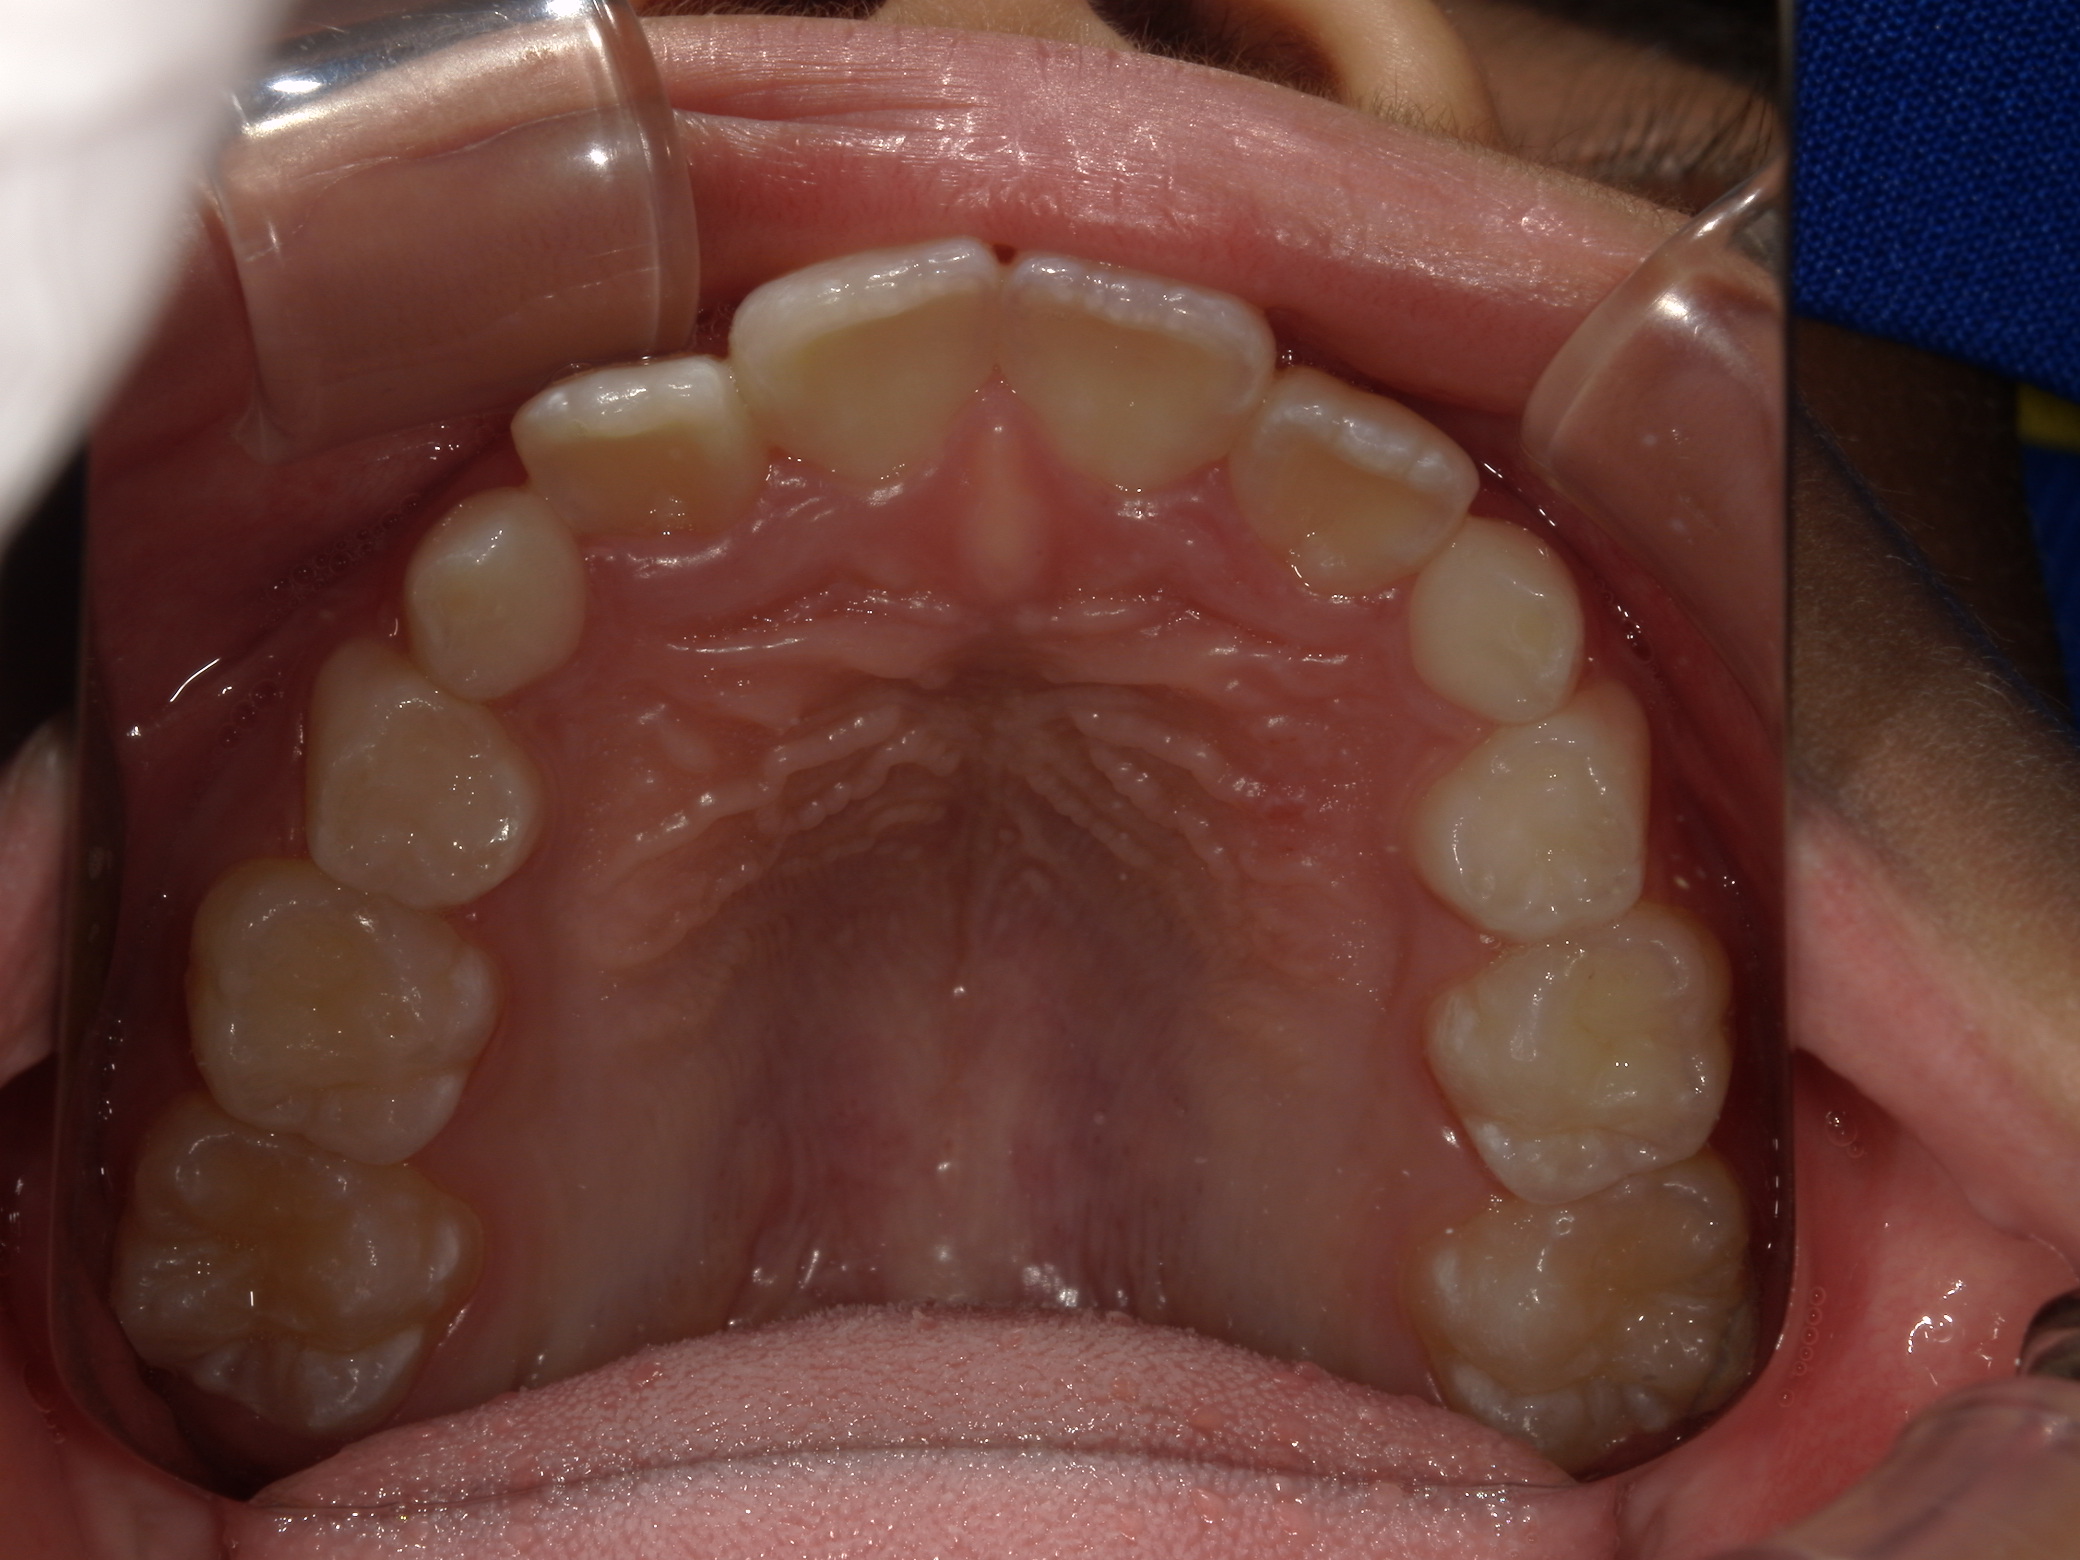

| 年齢・性別 | 8歳11ヶ月の男児 |

|---|---|

| 主訴 | 上顎の永久歯の位置がおかしいとのことで来院。萌出していない右上の前歯の状態に不安を抱えられていました。 |

| 治療期間・回数 | 約3年2ヶ月 |

| 費用 | 440,000円(税別) |